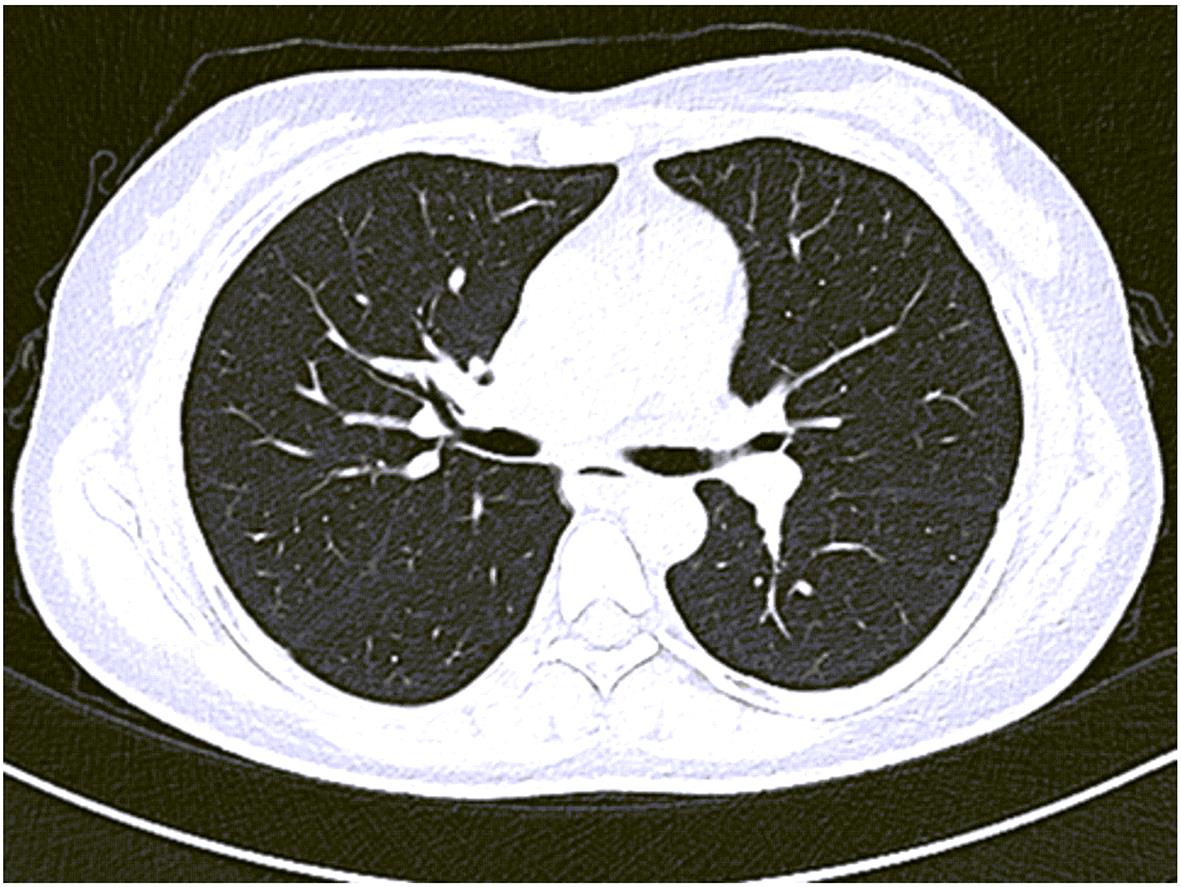

Accessory spleen refers to the spleen tissue that exists outside of the normal spleen, with a similar structure to the main spleen and certain functions. Intrapancreatic accessory spleen (IPAS) completely enveloped by the pancreas has an incidence rate of only 2%, and it is easily misdiagnosed in clinical practice due to its atypical clinical symptoms and similar radiological features to pancreatic neuroendocrine tumor, pancreatic solid pseudopapillary tumor, and other pancreatic space-occupying lesions. This article reports the clinical data of two patients with IPAS who were misdiagnosed as pancreatic neuroendocrine tumor and pancreatic solid pseudopapillary tumor, respectively, analyzes the reasons for misdiagnosis, and summarizes the experience in diagnosis and treatment, in order to improve the ability for the differential diagnosis of IPAS in clinical practice.